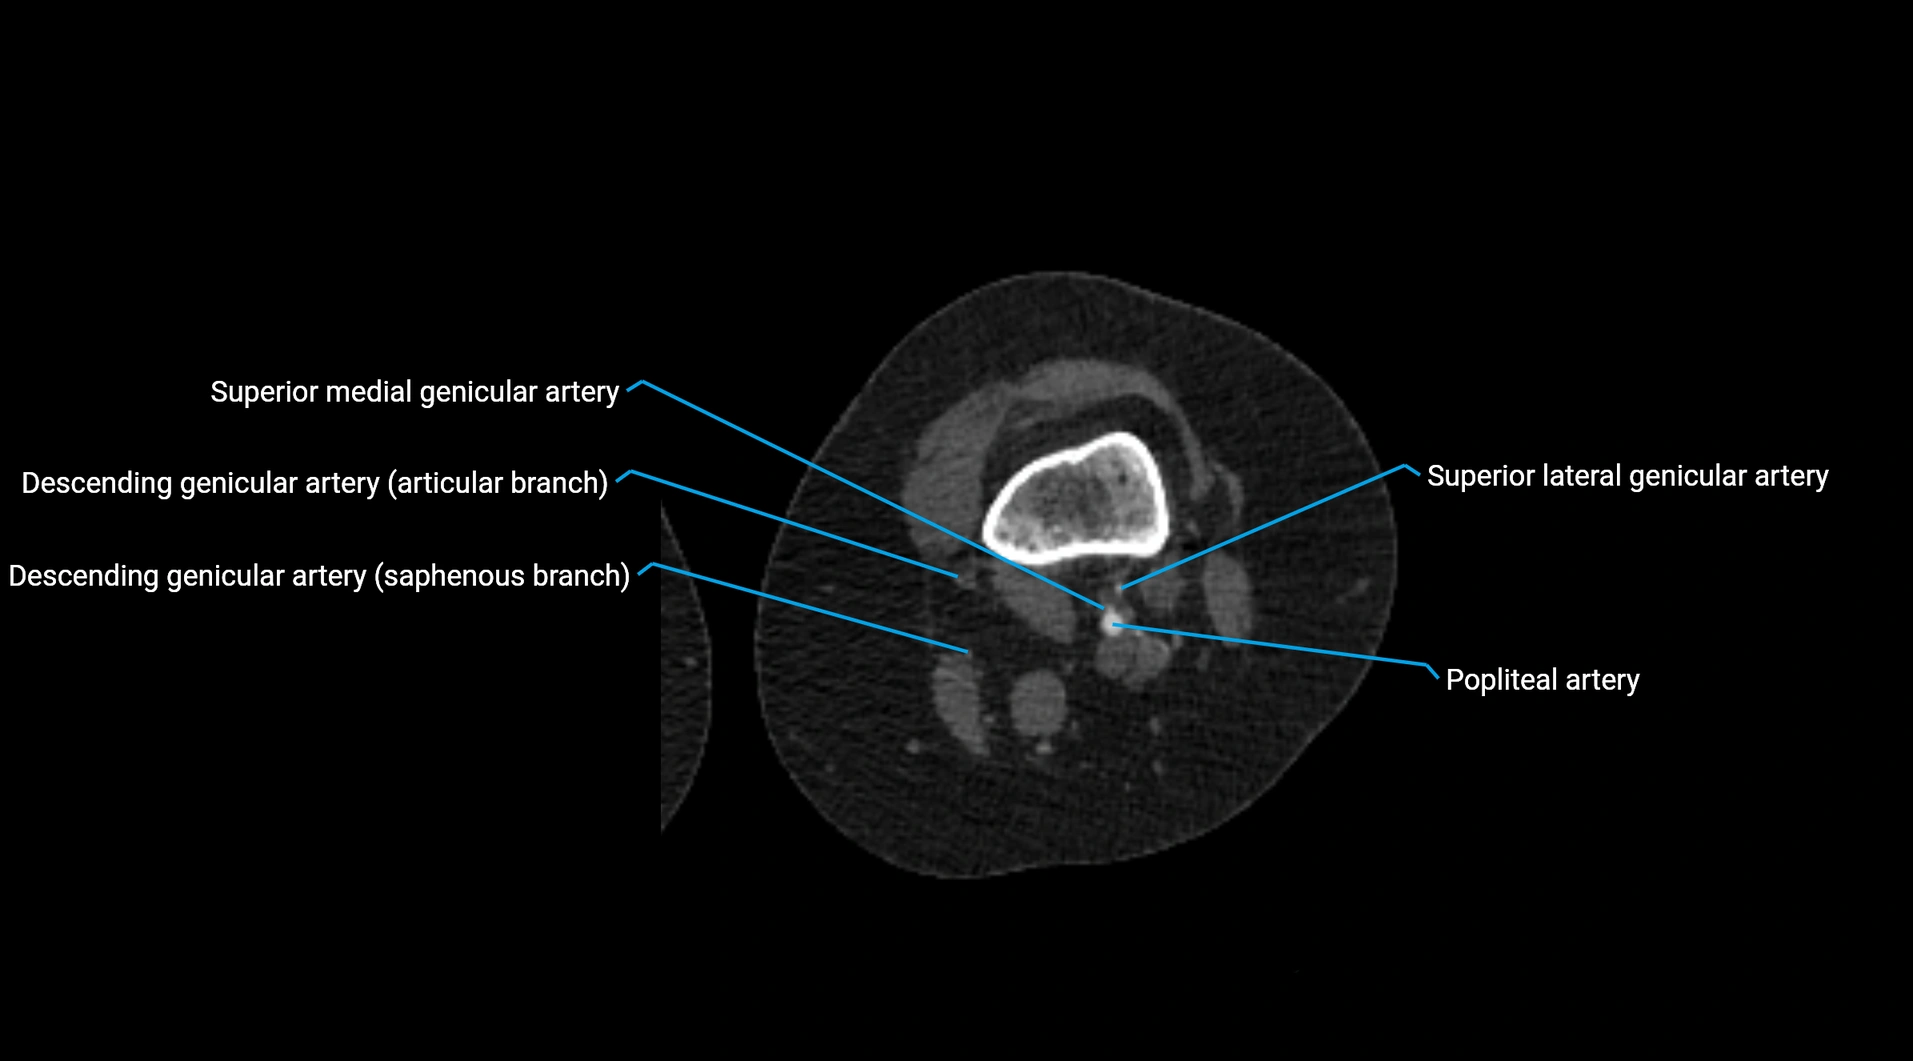

Contrast-enhanced CT (CTA):

• Gold standard for abdominal aortic imaging

• Provides excellent detail of lumen, wall, aneurysm, thrombus, and branch vessels

• Multiplanar and 3D reconstructions help in aneurysm measurement, stent graft planning, and dissection evaluation

• Detects acute rupture, traumatic injury, or occlusion with high sensitivity